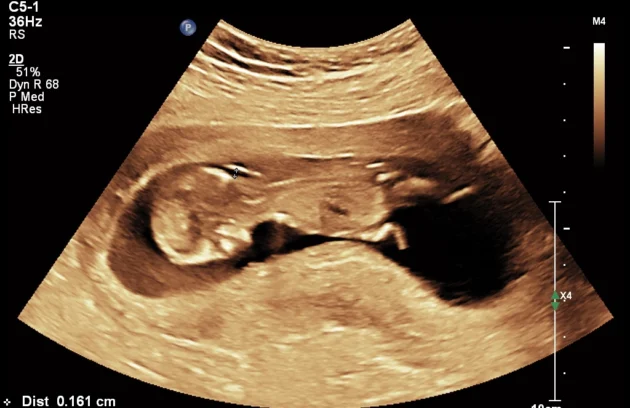

🔹 3D / 4D Ultrasound

3D/4D Ultrasound provides a clear and real-time view of your baby inside the womb. While 3D shows detailed images, 4D allows you to see live movements like smiling or yawning. It enhances bonding between parents and baby while also helping doctors assess physical development. Experience advanced 4D ultrasound in Kathmandu for a memorable and informative pregnancy journey.